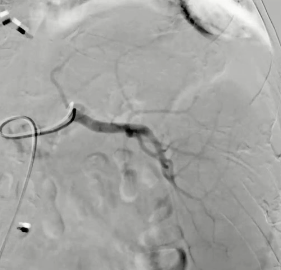

1. 血管内路径 endovascular

动脉瘤(假性) 阴茎深背静脉(勃起功能障碍) 消化道出血 Gl-bleeding ? 精索静脉曲张varicocele 盆腔淤血综合征(PCS) 门静脉栓塞 食管静脉曲张栓塞 主动脉支架内漏 动脉瘤样骨囊肿 ABC 肝癌 HCC 多发神经内分泌癌 mNET 转移性肾癌mRCC .......... 找到理想的患者是非常重要的 栓塞剂的种类,我们有很多可供临床选择和应用的栓塞剂,还有更多的产品在等待上市,或正在研究中 胶 Glue NBCA 碘油 Lipiodol Onyx 无水酒精 栓塞物的选择是 一项具有竞争力的决定,意味着一种临床情况,多种液体栓塞剂都在考虑中,甚至弹簧栓,血管塞,微粒栓塞材料。在很多情况下是栓塞材料的联合应用

栓塞材料的可及性(例如病灶栓塞材料的可到达性)accessability (e.g. reachability of the nidus) 栓塞的预期深度intended deepness of embolization 如果需要让栓塞填满最后1mm 预期效果(例如:门静脉栓塞的炎症)intended effect (e.g. inflammation in PVE) 凝血状态(达到止血效果所需的时间)coagulation state (duration until hemostasis) 并发症(过敏、心律不齐、肺动脉高压、肝纤维化等)comorbidities (allergies, arrythmia, pulmonary hypertension, lung fibrosis etc.) 处于危险中的结构(包括下游部分-downstream和反流部分) structures at risk (downstream & backwash) 靶病变定位(浅层与深层) target lesion localization (superficial vs. deep) 不会选择一些会引起炎症的东西,因为那会病人来说真的很痛苦浅层病变 栓塞所需的速度(例如:危及生命的出血情况)required speed of embolization (e.g. life threatening hemorraghe) 院外专业人员(DSA技术人员和介入放射科医生)local expertise (technicians & IR's) 可用性与定价 availabilty & pricing Patient assessment for the choice of the ideal liquid emboli 影像学 62岁 男性